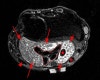

MRI : 손목 점액낭염(Wrist bursitis)

정밀검사를 위해 MRI를 적용할 수 있습니다.